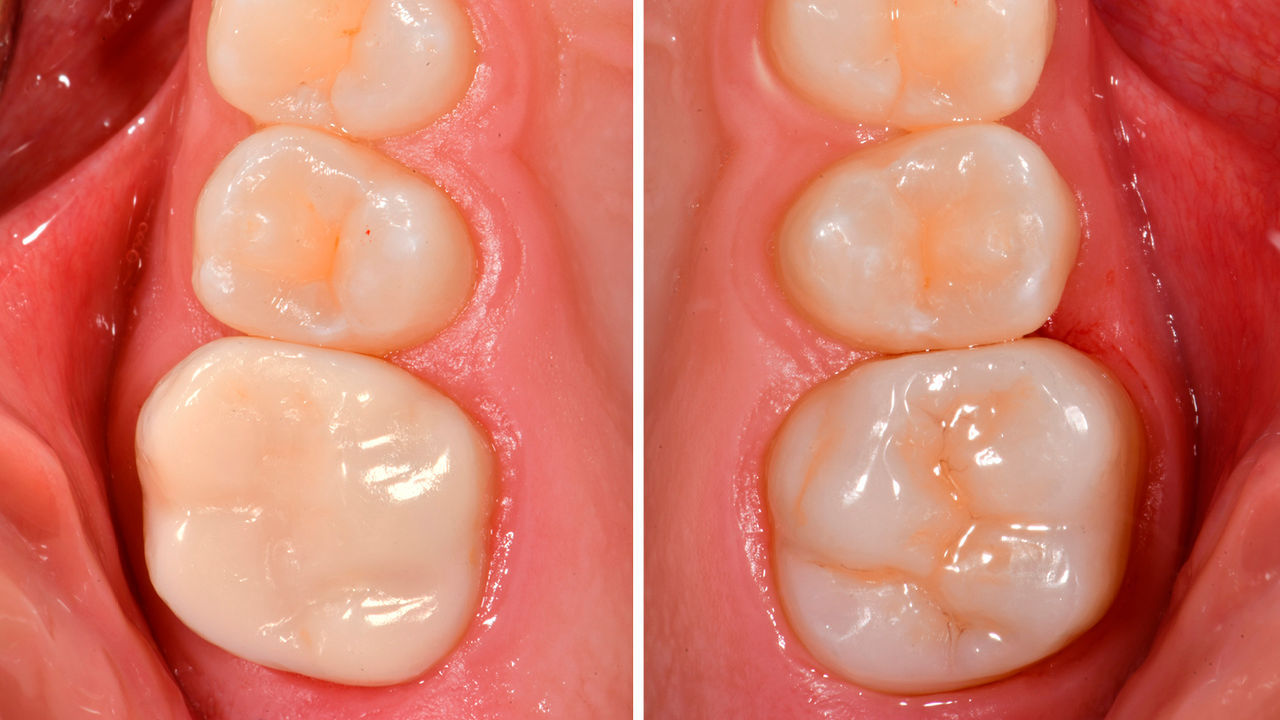

Avant : La première molaire maxillaire avait été restaurée avec un plombage composite étendu mais insuffisant qui présentait déjà des fractures visibles.

Après : Restauration fabriquée en consultation à partir d’une céramique avancée à base de disilicate de lithium, CEREC Tessera.